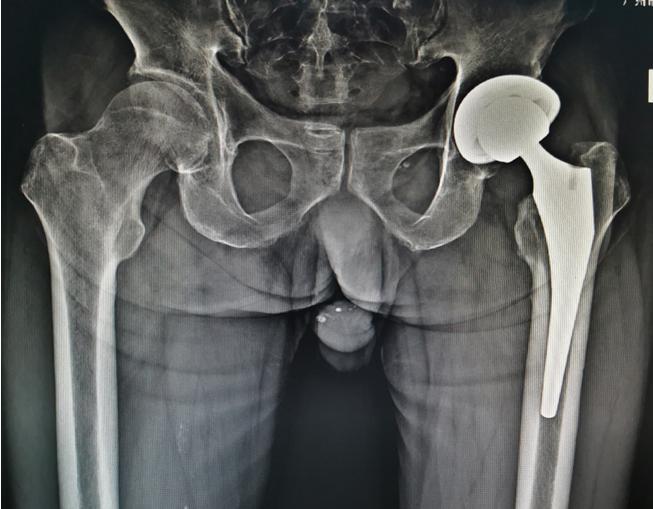

股骨颈骨折术后